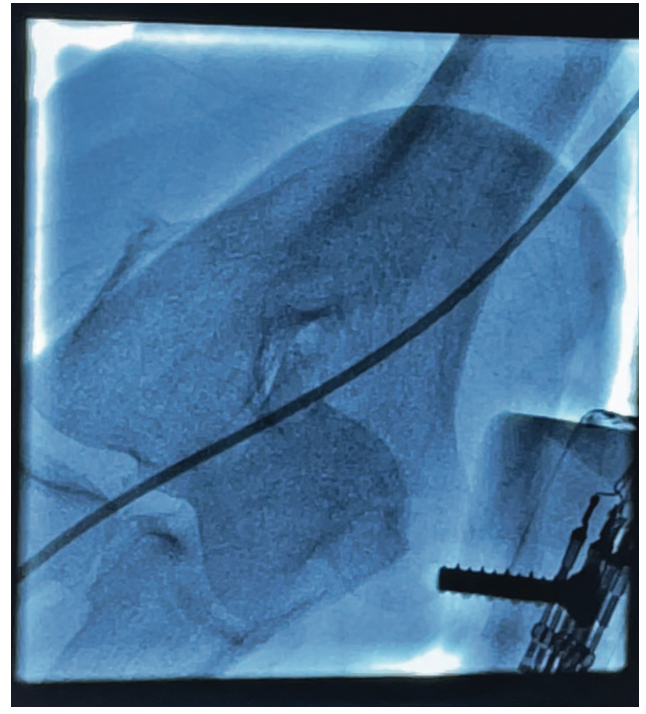

Kinked Catheter Unravelment in the Right Upper Extremity An Unconventional Solution

Kinked Catheter Unravelment in the Right Upper Extremity An Unconventional Solution Catheter Kinked below you’ll find information on some of the associated risks and problems you may encounter with a catheter. In some cases, your catheter may need to be changed. make sure the tubing is not twisted or kinked. Catheter blockage is an emergency and needs to be resolved as quickly as possible. if there are no kinks in. Catheter Kinked.

Kinked Catheter Unravelment in the Right Upper Extremity An Unconventional Solution Catheter Kinked check for kinks in the catheter or drainage bag tubing. Keep the catheter and drainage bag below the bladder and off the floor. if there are no kinks in your catheter or tubing, it is possible that your catheter is blocked. Diagnostic coronary artery catheter knotting and kinking are uncommon but potentially catastrophic complications. If the drainage bag. Catheter Kinked.

Kinked Catheter Unravelment in the Right Upper Extremity An Unconventional Solution Catheter Kinked this occurs when a catheter cannot drain and is most commonly caused by the catheter or tubing being kinked or occluded, or by constipation or the weight of a full catheter bag pulling the balloon into the bladder neck. below you’ll find information on some of the associated risks and problems you may encounter with a catheter. Diagnostic. Catheter Kinked.

Kinked Catheter Unravelment in the Right Upper Extremity An Unconventional Solution Catheter Kinked if there are no kinks in your catheter or tubing, it is possible that your catheter is blocked. Keep the catheter and drainage bag below the bladder and off the floor. this occurs when a catheter cannot drain and is most commonly caused by the catheter or tubing being kinked or occluded, or by constipation or the weight. Catheter Kinked.